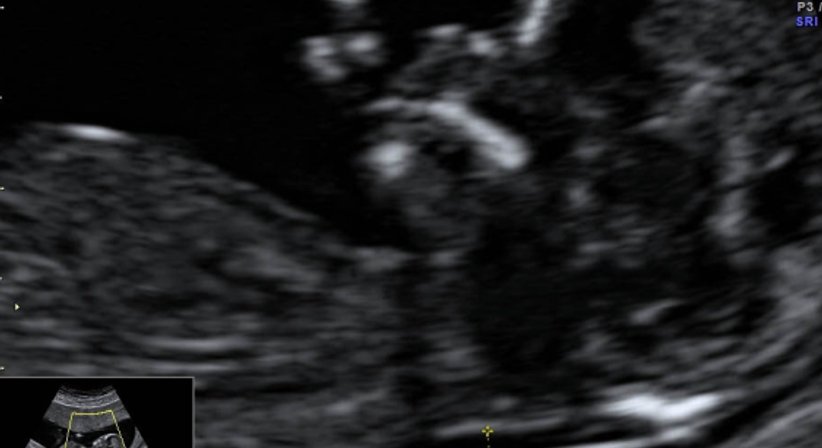

Bei nahezu allen gynäkologischen Untersuchungen mache ich natürlich auch eine Ultraschalluntersuchung des kleinen Beckens. Durch die sog. Vaginalsonde kann man sämtliche Strukturen exakt darstellen und mit der Patientin besprechen. Vor allem bei Eierstockzysten, Menstruationsstörungen und bei entzündlichen Veränderungen, wie Abszessbildungen u.a. ist der Ultraschall äußerst wichtig.

Mit verschiedenen Methoden können wir heute beurteilen, ob während der Schwangerschaft mit Mutter und Kind alles in Ordnung ist, oder ob Risiken vorliegen. Der Ultraschall hilft uns dabei als nahezu einzige Methode, das ungeborene Kind in der Gebärmutter direkt sichtbar zu machen.